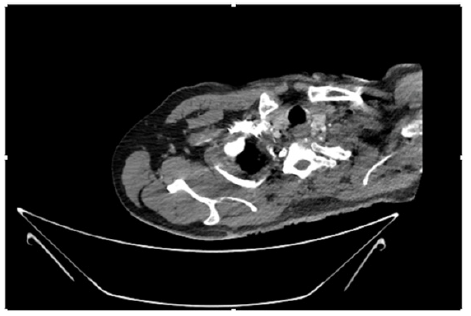

55-years-old chronic smoker had acute, severe pain in the right upper limb for one week; it was cold upto mid arm with skin discoloration. He also noticed numbness and weakness of movement of elbow joint. He underwent below elbow amputation in February 2023 for acute ischemia of left upper limb. He was a current chronic smoker; 15 pack year. General condition was weak; temperature was normal; blood pressure was 100/60mmHg; heart rate was 92/minutes with sinus rhythm; SpO2 was 97% on air; heart was normal. In lower extremities, all peripheral pulses were intact. Local Examination of right upper limb revealed as follows: tenderness; coldness; discoloration; decreased motor function and sensory modalities. Axillary, brachial and radial pulses were not palpable. Hand-held Doppler failed to detect any signal in arterial system; therefore, we arranged for emergency embolectomy. complete occlusion of right upper limb arterial system Full blood count showed high hemoglobin (14.6gm%); normal total WBC and platelet count. Coagulation profile was normal. Parenteral unfractionated heparin, antibiotics, tramadol, proton-pump inhibitors, anti-platelets and HMG CoA reductase inhibitors were given. Doppler ultrasound demonstrated complete occlusion of right upper limb arterial system. CT Angiogram illustrated occlusion of subclavian artery downwards on both sides. Figures 1-14 shows complete occlusion of right subclavian artery without collaterals. On Day ‘2’ of admission, the patient passed black tarry stool for 3 times. However, the vital signs were stable; blood pressure was 100/60mmHg; heart rate was 92/min; SpO2 was 97% on air; the abdomen was soft and not tender. Above elbow amputation was done on Day ‘2’ of admission. Intra-operative findings were as follows: (1) no active bleeding at brachial artery; (2) thrombosis along brachial artery; (3) muscle color and consistency were not healthy.

Figure 10: CT Angiogram at upper arm showing totally occluded right axillary artery; normal internal carotid artery and external carotid artery.